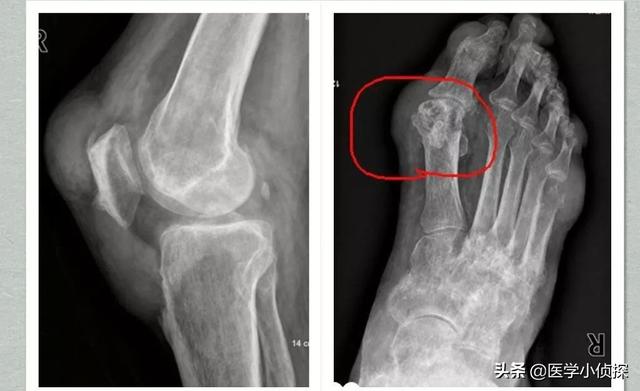

La deuxième étape consiste à effectuer une étude d'imagerie, par exemple pour détecter un "signe de double piste" sur l'échographie ou pour effectuer un "signe de double piste" sur l'échographie.La tomodensitométrie à double énergie révèle des dépôts d'urateetc., puis ouLes radiographies révèlent un gonflement des tissus mous, une destruction des bords du cartilage et une irrégularité des surfaces articulaires.!

La goutte peut être détectée par imagerie, la présence de cartilage articulaire "signe de double piste", l'épanchement articulaire, l'érosion osseuse, etc., peuvent également être diagnostiqués par des indicateurs de la fonction rénale.

Quel est le diagnostic standard et précis dans les hôpitaux ?

À ce jour, plusieurs critères de classification (diagnostic) de l'arthrite goutteuse aiguë ont été proposés au niveau international, tels que les [Critères de Rome] publiés en 1963 et les [Critères de New York] publiés en 1966, qui ont tous deux été remplacés en raison de leur sensibilité et de leur spécificité insuffisantes.Les critères de classification (diagnostic) de 1977 de l'American College of Rheumatology sont largement utilisés dans la pratique clinique.

- (10) Tuméfaction intra-articulaire asymétrique (confirmée par radiographie)

- (11) Kyste sous-cortical de l'os sans érosion osseuse (confirmé par radiographie)